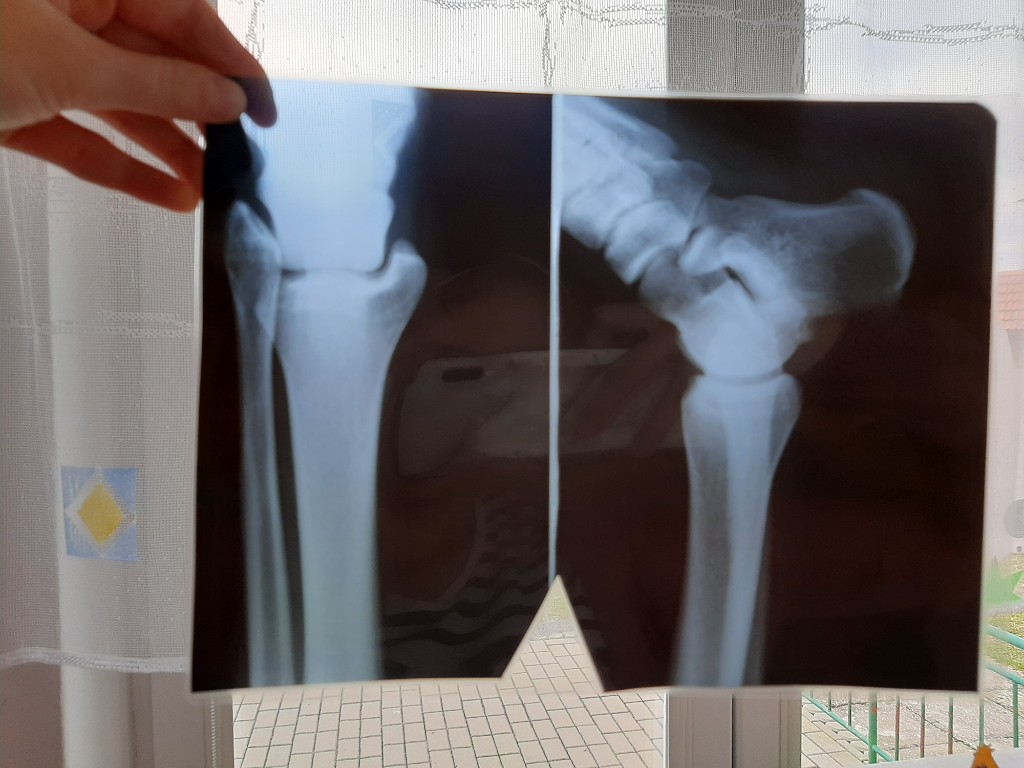

První pomoc v MŠ

Datum: 22. 4. 2022 | Počet fotografií: 279